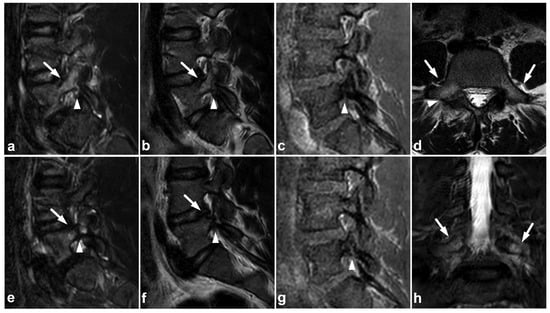

Figure 19.

(a) Sagittal right-sided off-midline STIR. (b) Sagittal right-sided off-midline T2-weighted. (c) Sagittal right-sided off-midline black bone sequence. (d) Axial T2-weighted. (e) Sagittal left-sided off-midline STIR. (f) Sagittal left-sided off-midline T2-weighted. (g) Sagittal left-sided off-midline black bone sequence. (h) Coronal STIR. A 12-year-old female with acute lower back pain when playing with friends. MRI demonstrates bilateral bone marrow edema centered in pars interarticularis (arrows). Fracture lines are also seen bilaterally in the pars (arrowheads). No spondylolisthesis is present.